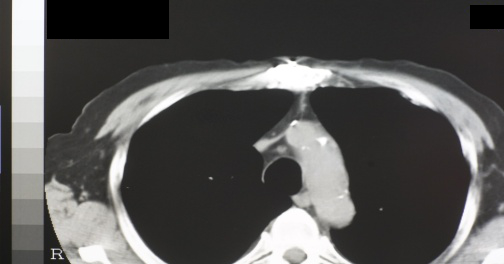

(3)造船労働者の胸部XP/CT写真の胸膜プラーク所見

私たちは1989年から2016年時まで退職した造船労働者の健康管理を27年間行った5)。退職後長年観察した例は稀で胸膜プラークの変化に着目した。15年間以上毎年胸部X線写真を撮影、胸部CT写真を10年間以上で3回以上撮影した「石綿肺管理2以上+続発性気管支炎」で労災認定された23名を対象とした(初回管理2以上17名、中間時管理2以上6名)。医師3名が独立して初回、観察中間時、最新回の胸部XPと胸部CT写真を読影、医師間の所見の異なる写真は再意見を求め再意見の各自読影結果を最終結果とした。対象は全員男性、現在・死亡時平均年齢は87歳(80~96歳)、初診時平均年齢は64歳(58~72歳)従事年数は平均35.3(17~41)年、職種は溶接7名、機関6名、ボイラー4名他6名で、非喫煙3名・前喫煙20名・現喫煙0名で平均喫煙係数611(220~1520)だった。2016年現在生存14名、死亡9名(平均年齢86.1<80~90>歳)、胸部X線写真観察期間は平均21.5(15~26)年で医師の読影所見は22名で一致した5)

1. 初回~最新回XPとCT共に胸膜プラーク有9名(39.1%)平均年齢65.1(62~72)歳【写真1】

3. 初回XP胸膜プラーク無・CT有7名(30.4%)平均年齢73.4(66~80)歳【写真2】

5. 初回XP/CT胸膜プラーク無・最新回XP無・CT有は3名で【写真3】胸膜プラークの確認時年齢は69・77・80歳、80歳時点の胸部CTはプラーク検出に有意義だった。

7. 初回~最新回CTで胸膜プラーク無4名中3名永眠(80~84歳)し85歳1名が生存中。

9. 23名中肺癌が3名に発症し発症時年齢79、81、88才で、円形無気肺を 2名に認めた5)。

【写真1】胸膜プラークの胸部X線写真 典型的な経過5)

【写真2】初回XP胸膜プラーク(-)初回CT胸膜プラーク(+)

【写真3】初回CT胸膜プラーク(-)最新回CT(+)

胸部X線写真で胸膜プラークのある場合、胸膜プラークは経年的に厚く大きくなり徐々に石灰化した【写真1】。胸膜プラークはCTで66~80歳で初めて認められ、70台,80才の胸部CT写真撮影の必要性が認められた【写真3】。高濃度石綿ばく露をうけた23名中4名に80台でも胸部CTで胸膜プラークのない群が確認された。肺がんによる死亡が3名に認められ、胸膜プラーク有は1名で2名はXP・CT共に最後までプラークなしだった。職業性石綿ばく露を受けた集団は、退職から永眠までの期間の健診体制を必要とし、胸部X線CT写真を併用し観察する意義が再確認された5)